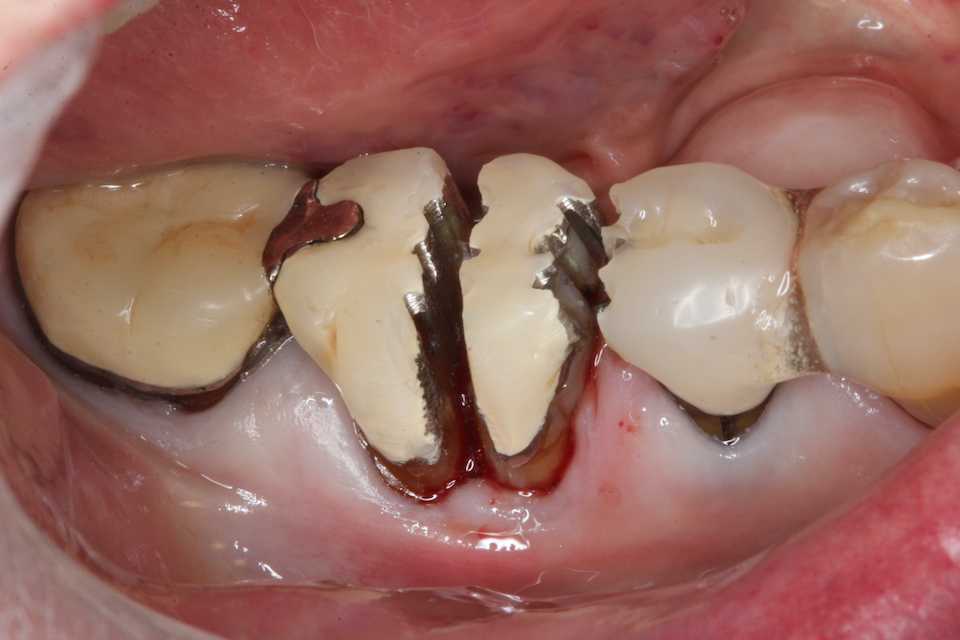

88歳女性、咬合性外傷、食いしばりがひどいとかで、また咬合力も強い。骨隆起を見れば歯を酷使してきたことが分かると思う。何度も歯根破折やPerで再植等を繰り返したが、とうとう右下56の歯根が砕けて抜歯になってしまった。入れ歯は嫌だ、、とおっしゃる。僕も入れ歯は手間がかかるので嫌なので、細い咬合負担の少ないブリッジ風の接着性義歯を作った。外注したくても義歯の外注先が廃業、絶滅してしまった。こんなものはCAD/CAM、3Dプリンター等の機械では作れない。歯科技工士が絶滅してしまったら、患者は歯は抜きっぱなし、土手で食べてね。。ということになる。そういう歯科治療難民の近未来の状況は地方から燎原の火の様に日本中を焼き尽くすことになるだろう。最後の再植は10年程前のお話。そこからアップしてみます。補強連冠を入れて頑張ったのだが、とうとう歯根が折れて、どうなっているのかよく分からないがひどい炎症がある。流石にこんなになっては患者も抜くしかないと思う。抜歯後、接着性の義歯を作った。ご本人は大切に使いますとおっしゃるが。。骨隆起を見ればどういうことなのかよく分かると思う。